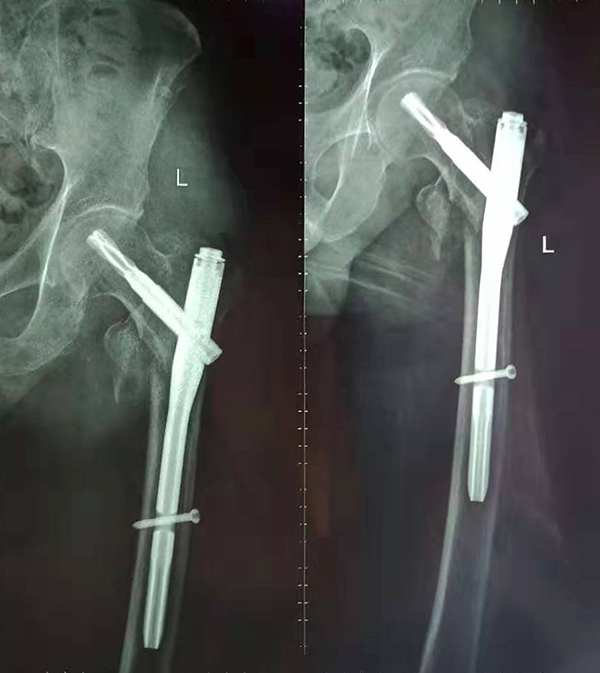

經(jīng)術(shù)前仔細(xì)的檢查和評估,與張爺爺家屬充分溝通,決定了實(shí)施閉合復(fù)位PFNA內(nèi)固定術(shù)的方案,劉鴻程主任說到,該術(shù)式的創(chuàng)傷小、出血少,適合骨質(zhì)疏松病人,術(shù)后解除患者疼痛,可以早期開始活動(dòng),便于護(hù)理。

手術(shù)前

手術(shù)后

9月10日上午,骨科順利完成張爺爺?shù)淖蠊晒谴致¢g骨折髓內(nèi)釘內(nèi)固定術(shù)。手術(shù)過程中麻醉平穩(wěn),術(shù)中出血量少,骨折手術(shù)時(shí)間持續(xù)一個(gè)多小時(shí)。